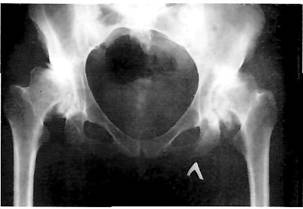

Рис. 10. Рентгенограммы больных с различными стадиями асептического некроза головки бедренной кости: а - начальная стадия аваскулярного некроза: отсутствие рентгенологических признаков; б - остеолиз костной ткани верхнего сегмента головки бедренной кости без признаков ее импрессии и деформации; в - рентгенологическая картина сходна со 2 стадией, но имеются начальные признаки коллапса; г - типичная картина асептического некроза головки бедренной кости: импрессионный перелом субхондральной кости с формированием зоны коллапса в наиболее нагружаемом сегменте головки бедренной кости; д - поздняя стадия остеонекроза: разрушение верхнего сегмента головки бедренной кости, кистозные изменения сохранившейся части головки и шейки бедра, деформация вертлужной впадины, резкое сужение суставной щели.